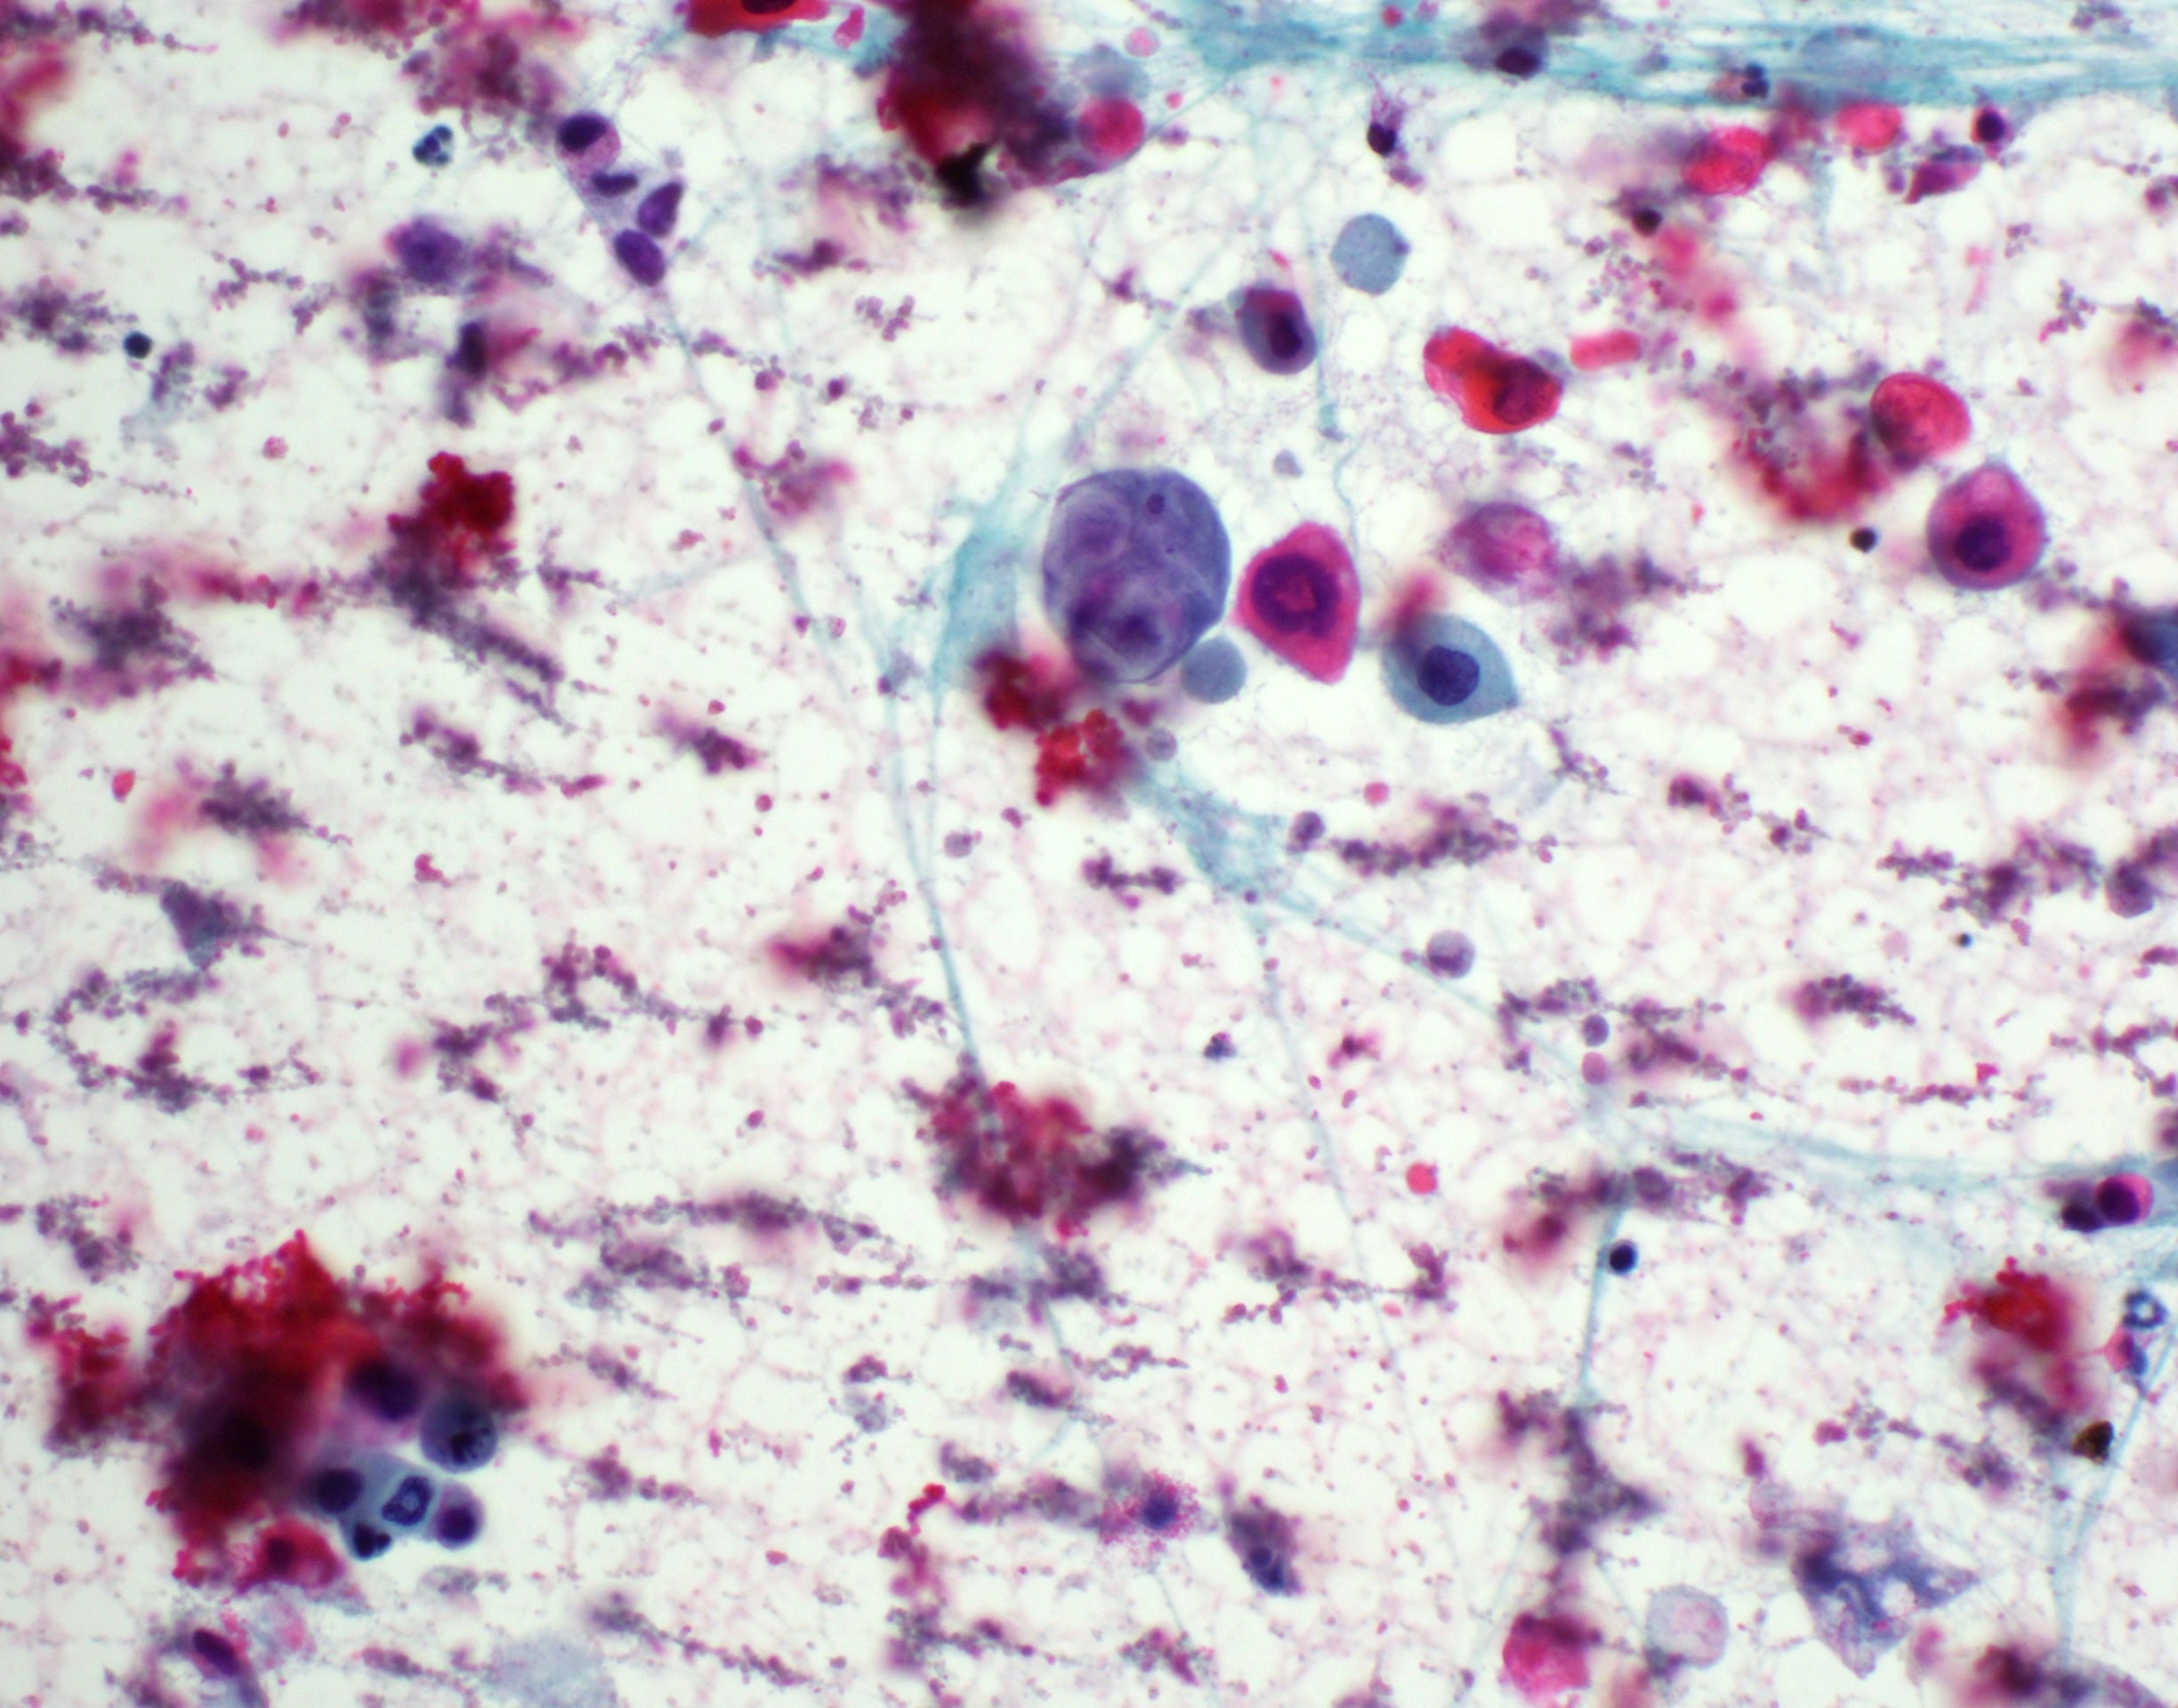

Cytology description

- Role of cytology only in investigation of regional or distant metastases

- Appearance depends on type and differentiation

- Conventional squamous cell carcinoma shows sheets and small clusters of large polygonal malignant cells with intercellular bridges and cytoplasmic or extracellular eosinophilic keratin

Cytology images